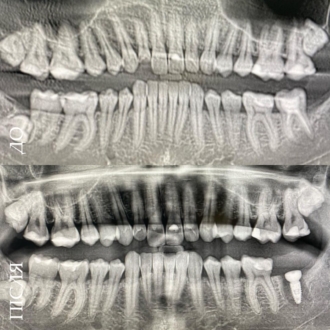

Пациент обратился с жалобами на повышенную чувствительность к воздуху и сладкую пищу в области угловых зубов. После обследования и диагностического разбора КТ был диагностирован глубокий контактный кариес 14 и 15 зуба. Произведено изолирование зубов кофердамом, с последующим раскрытием кариозных полостей и последующим восстановлением утраченных тканей методом художественной реставрации.